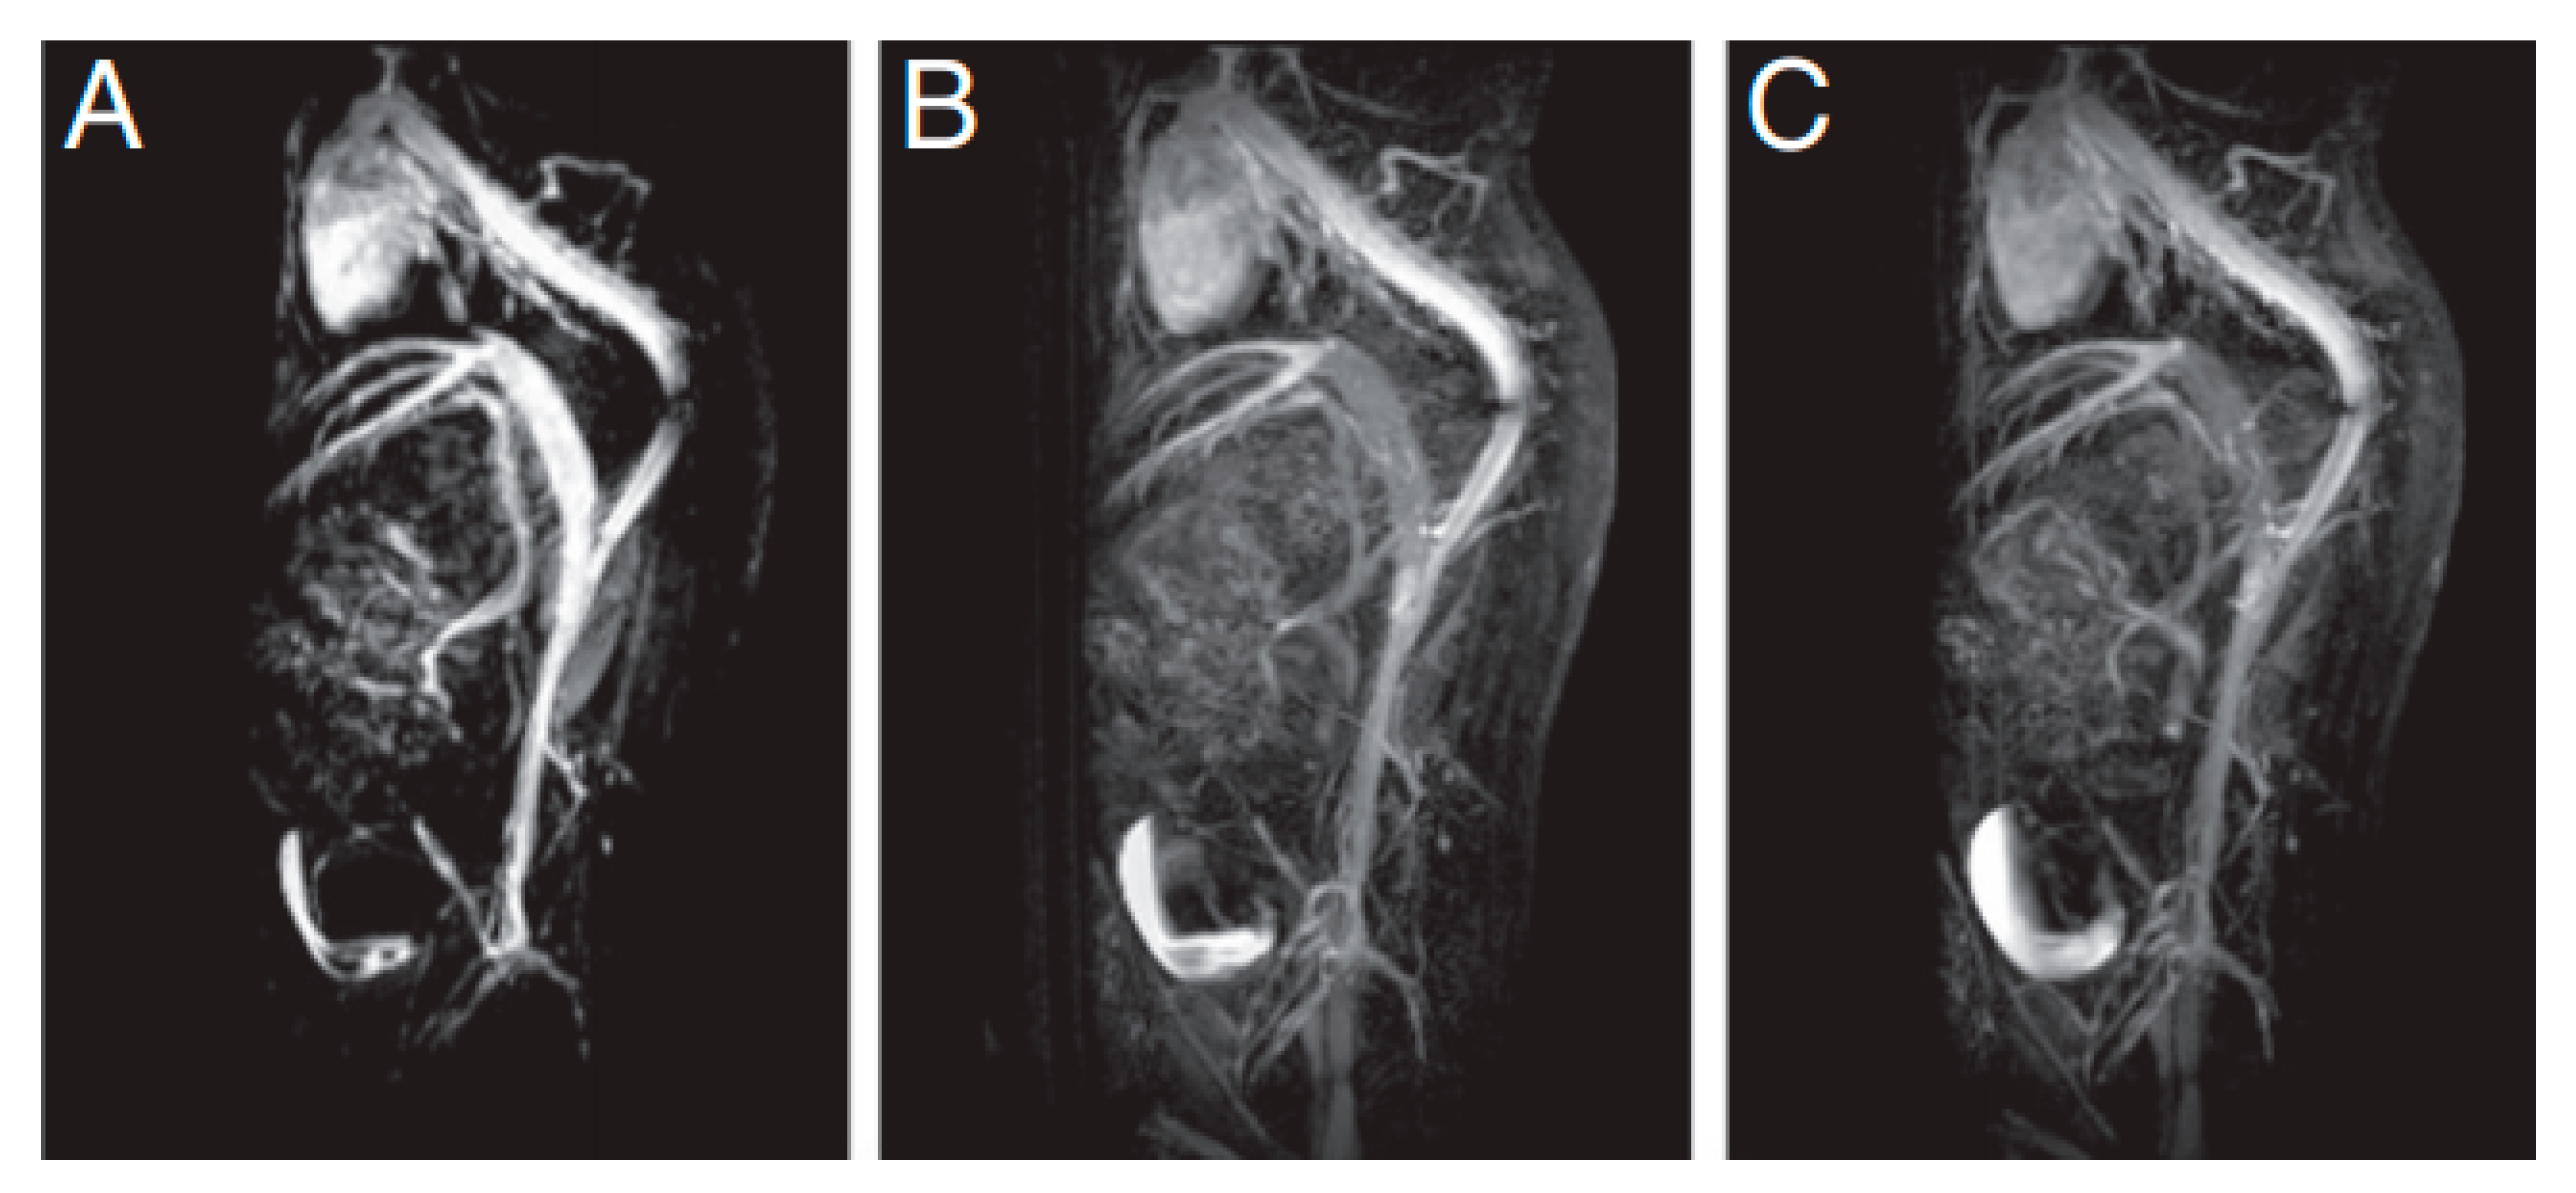

- Vangijzegem, T.; Stanicki, D.; Boutry, S.; Paternoster, Q.; Elst, L.V.; Muller, R.N.; Laurent, S. VSION as high field MRI T1 contrast agent: Evidence of their potential as positive contrast agent for magnetic resonance angiography. Nanotechnology 2018, 29, 265103. [Google Scholar] [CrossRef]